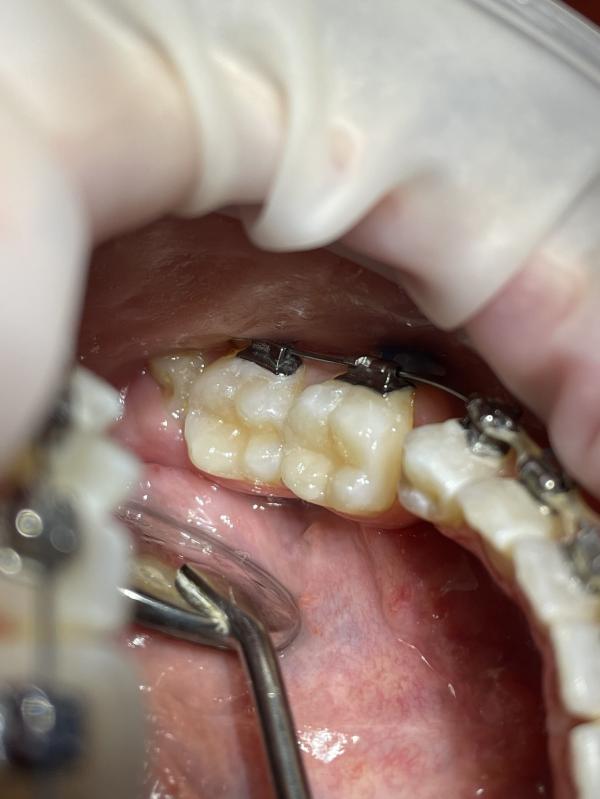

на фото представлено

Это кариес в области фиссур зуба, вот как на фото ( в углублениях черное то что вы видите) если не лечить такой кариес через 1/2 года зуб разрушается, появляются сильные боли, воспаляется пульпа(пульпит)